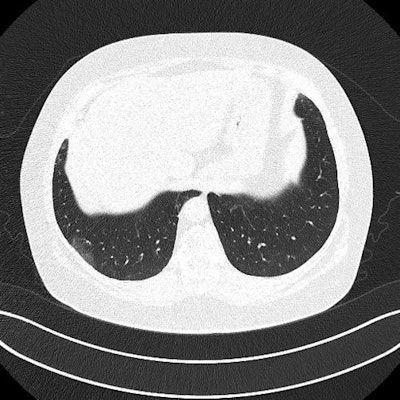

Ultrasound and CT images from a 62-year-old woman with long-term COVID-19 symptoms. The patient, who was not part of the study, visited the Madrid emergency department with persistent dyspnea and cough. The ultrasound image (above) shows an irregular pleural line and some B-lines, which correlate to ground-glass opacities in the lower lobes on CT (below). Images courtesy of Dr. Yale Tung-Chen, PhD.

The three patients in the study, which was published in the Journal of Ultrasound in Medicine, had mild cases of COVID-19 but lingering shortness of breath. Ultrasound scans revealed a variety of pulmonary findings, including irregular pleural lines and B-lines, which correlated with abnormalities on CT scans.

- The 35-year-old woman had a mild, irregular pleural line and B-lines in her right anterior chest on ultrasound, which correlated with ground-glass opacities on CT.

- The 41-year-old woman had an irregular pleural line in her right lateral area on ultrasound, which correlated with pleural thickening on CT.

- The 64-year-old man had a marked, irregular pleural line and multiple B-lines on ultrasound, which correlated with fibrotic changes on CT.